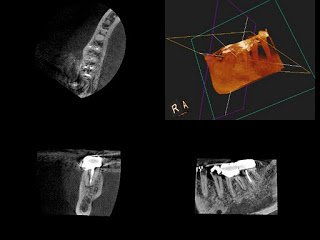

The tooth was slightly tender to bite forces and percussion, but there was again no signs of swelling or a sinus tract. The probing depths were 2-3mm with a 7mm pocket on the MB and a 6mm pocket on the DB. Because of the bilateral probing and bone loss, and the symptoms unchanged with root canal treatment, I recommended a periodontal evaluation. I knew that there was an untreated MB2, but the periodontal symptoms did not match up. After periodontal treatment, the pocket on the distal resolved, and there was a short-term improvement in symptoms, but they soon returned. At this point, I was suspicious of a perforation. A CBCT would certainly help confirm the diagnosis and be of value, but a decision was made to access and investigate.

At the first visit, the patient was made aware of a fracture from the mesial to the distal that dramatically decreased the prognosis for the tooth. After the first visit, the patient’s symptoms resolved, and she could chew comfortably. A case could be made to have the tooth immediately extracted, but the patient opted to finish the treatment even with the uncertainty involved.